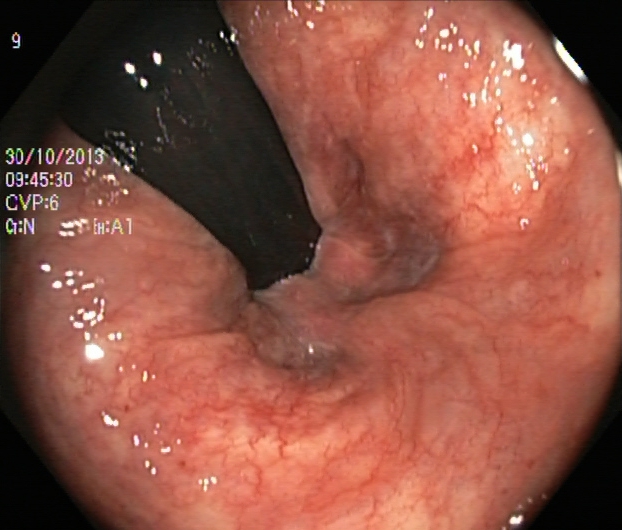

An automatic and efficient Computer-Aided Diagnosis (CAD) system in a clinic could assist medical experts during the endoscopic and colonoscopy procedure to improve the detection rate by finding unrecognized lesions and act as a second observer by providing better insights to the gastroenterologist concerning the presence and types of lesions. With this inspiration, we conducted five experiments to classify 161616 classes of GI tract conditions for the Medico Multimedia Task at MediaEval 2018 (Pogorelov et al., 2018b). One example for each of the 16 classes is depicted in Figure 1.

Figure 1. Sample images of GI findings. Each image represents one of the 16 classes from the dataset used for the Medico 2018 challenge (Pogorelov et al., 2017c, a).